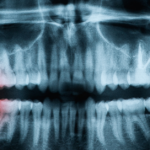

• Radiografie si CT dentar, totul într-un singur loc, la Clinica Doctor M - Investigația radiologică precum radiografia și CT-ul sunt instrumente esențiale pentru un diagnostic stomatologic corect și complet. La Clinica Dr.M din Craiova, ne ajutăm de această tehnologie pentru a identifica probleme precum cariile, infecțiile sau afecțiunile osoase care nu sunt vizibile cu ochiul liber.  Când este recomandată o astfel de investigație? ✅ Înainte de tratamente stomatologice...